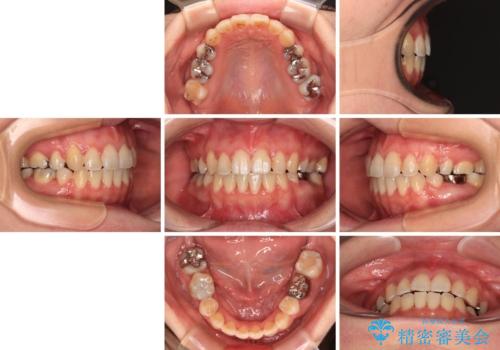

マウスピース(インビザライン)はほとんど使用することができませんでしたが、補助装置により上顎の八重歯は改善しておいたので、ワイヤー装置ではスムーズに治療を終えることができました。

- 3年10ヶ月

- 10-30回